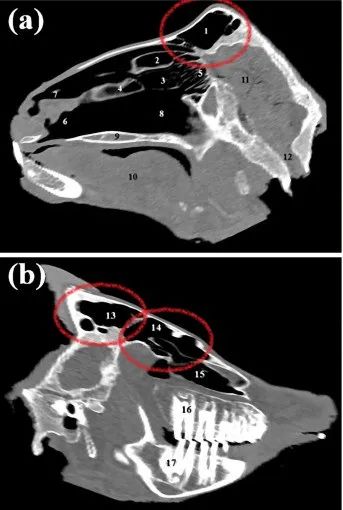

大角羊疏松多孔的角芯 | Trevor G. Aguirre et al. / Scientific Reports (2020)大角羊不仅会撞角,还会用角撞击对方的额头,所以角不会是唯一的减震措施。另一个经常被猜测为减震器的部分是额窦(frontal sinus)。额窦是骨头构成的两个空腔,一般位于从鼻根到额头的位置。人类的额窦只有大概3厘米高,大角羊和其他一些羊类的额窦巨大,甚至延伸到了角芯里,不禁让人怀疑,它应该有什么特别的作用。

山羊头的断层扫描图,圈出的部分是额窦 | Mohsen Tohidifar et al. / Anatomical Science International (2020)血管充当减震?